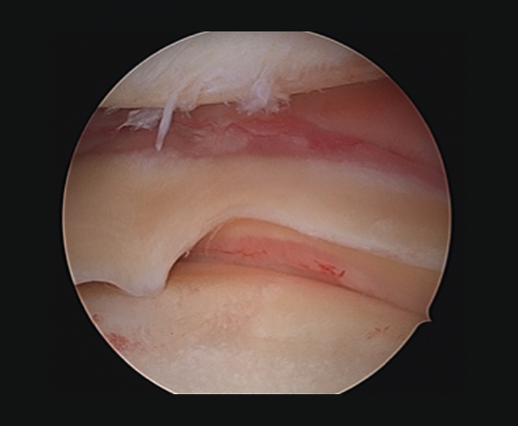

Meniscal root lesions

Meniscal root lesions are lesions located at less than 1 cm from the bone insertion of the meniscus, or lesions that involve bone avulsion of the anchoring zone (Figure 4). While lesions of the posterior root of the medial meniscus are related to degenerative processes, lesions of the posterior root of the external meniscus are associated to lesions of the ACL (7-12%)(30). Rupture of the posterior root of the medial meniscus biomechanically behaves like a total meniscectomy(31), while rupture of the posterior root of the external meniscus associated to ACL rupture results in an increase in anterior translation of the tibia and adds increased rotational instability, incrementing pivot shift(32).

[[{"fid":"4713","view_mode":"default","fields":{"format":"default","alignment":""},"type":"media","field_deltas":{"4":{"format":"default","alignment":""}},"link_text":null,"attributes":{"class":"media-element file-default","data-delta":"4"}}]]

Diagnosis

From the clinical perspective, these lesions should be suspected in the presence of Lachman scores of 3+ and pivot shift. High field MRI has been shown to be the diagnostic imaging test with the greatest sensitivity and specificity(33). Three radiological signs are associated to damage to the posterior root: 1) a hyperintense signal perpendicular to the meniscal root in the axial plane; 2) a vertical lineal defect over the meniscal root (truncation sign), which is associated to a meniscal extrusion of over 3 mm; and 3) the "ghost sign", representing the absence of meniscus in the sagittal plane in the zone of the posterior root(34,35).